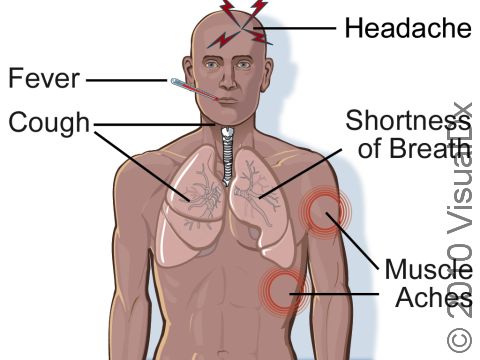

Inhalational Anthrax

Early symptoms:

- Cold or flu-like illness

- Fever

- Aches

- Sore throat

Later symptoms:

- Cough

- Chest pain

- Shortness of breath